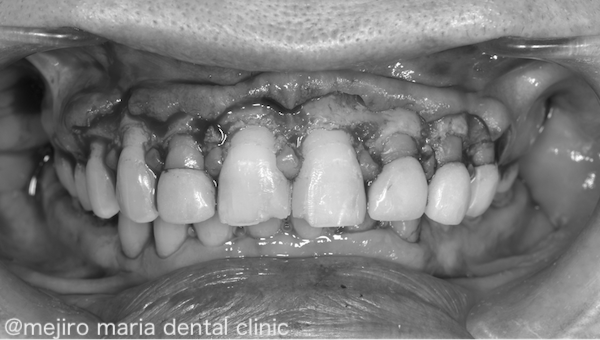

今回の患者様のガミースマイルの原因は、「受動的萌出遅延」です。受動的萌出遅延とは、歯が生えてくる過程で歯周組織に適切な変化が起きず、歯に多くの歯肉がかぶさってしまった状態を指します。

そこで、歯の見える部分を人工的に延長する「歯冠長延長術」という治療を行いました。歯肉のラインを整え、歯肉の内側の歯槽骨の位置と厚みも、適正にコントロールしました。